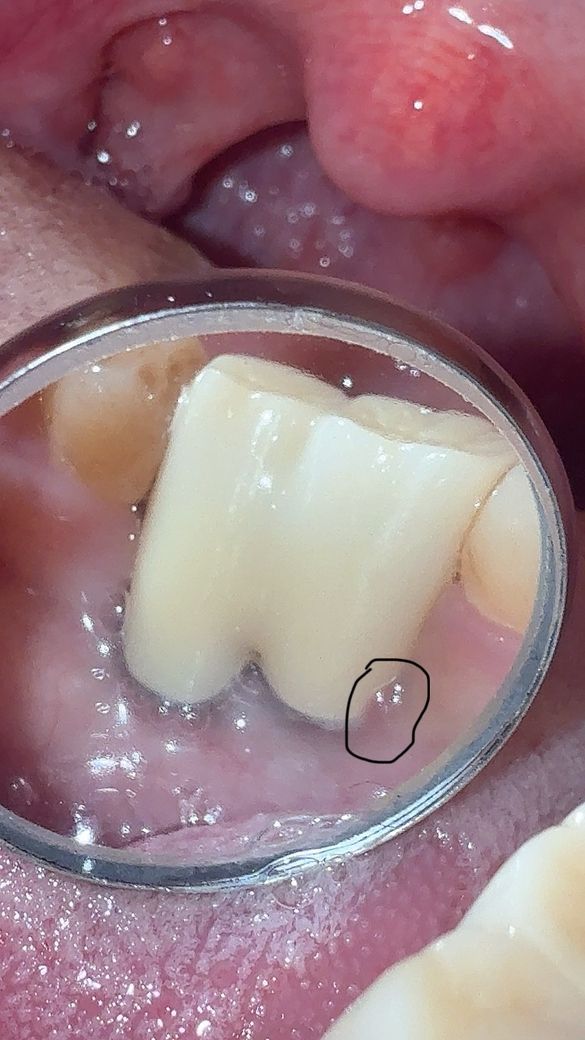

임플란트 주위염인지 봐주시면 감사하겠습니다

최근 타 치과에서 임플란트 주변 플라그 청소를 받고나서 1주일정도 지났습니다.

임플란트를 하고나서 나름의 관리 차원으로 치실,치간칫솔,워터픽,어금니 칫솔등을 사용하긴 했는데 이런 경우는 처음이라서요

체크부위가 아프거나 불편감은 없고 고름이나 출혈등은 없습니다

• 1번 째 사진

사진으로 봤을 경우에는 임플란트 주변으로 염증의 소인이 보이고 있습니다. 잇몸에 염증이 있다면 염증원인을 제거해야 합니다. 치석등으로 인해서 생기는 염증이라면 잇몸치료등이 필요할수 있습니다.

자세한 확인을 위해서 병원에서 진료를 받아보는 것을 권유드립니다.

약간의 염증상태로 보이나 최근 치과에서 잇몸처치를 받으셨다면 또 치과를 갈 필요는 없습니다 평소처럼 양치질, 치실질 잘해주세요